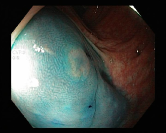

4.1.7 Gastrointestinal endoscopy

Endoscopies are used to detect diseases in the human digestive system. Images from inside the gastrointestinal tract can be used to help doctors detect diseases early. The used dataset 777https://www.kaggle.com/datasets/abdallahwagih/kvasir-dataset-for-classification-and-segmentation contains eight image categories of the digestive system obtained through the endoscopy imaging technique, as shown in Fig. 8. There are a total of images that can be used in training and testing machine learning algorithms.

Table 1 provides a detailed summary of the datasets used in this study, highlighting the total number of images in each dataset, the distribution between training and testing sets, and the specific classes represented. Each dataset corresponds to a particular medical imaging domain with distinct classes relevant to diagnosing specific conditions. Also, Fig. 9 presents a representative image from each dataset, allowing for a visual comparison of the diverse tones, patterns, and textures present across the datasets. Such diversity in visual characteristics highlights the need for a robust model that can handle all image characteristics.